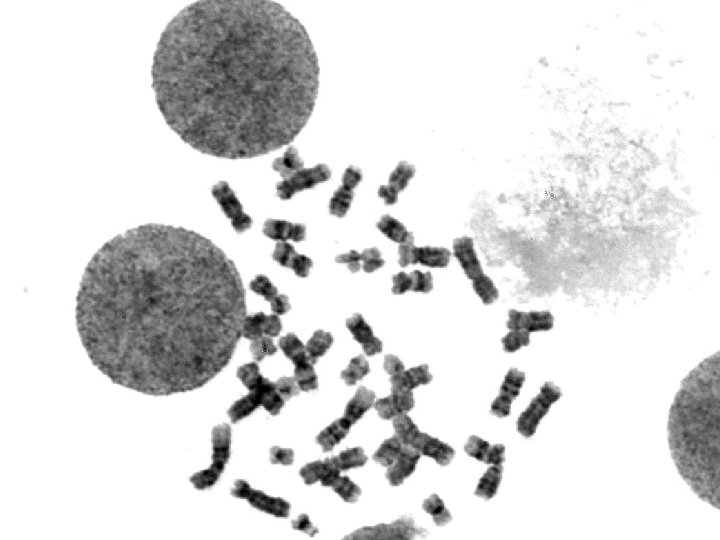

ISCN: 46, XX, t(8; 21)(q 22; q 22)[19]/46, XX[1]

FISH analysis with the AML 1/ETO-DF probe Acute myeloid leukemia with t(8; 21)(q 22; q 22) 94% of cells show a dualfusion signal pattern, i. e. the AML 1/ETO fusions